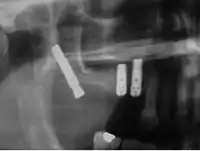

Cigomáticos

Son implantes autorroscantes de longitudes entre 30 a 52,5 mm y una cabeza angulada de 45° que se introducen en el hueso cigomático. Su porcentaje de éxito varia entre 80 y 95 % .Son una alternativa a los injertos de hueso en maxilar atróficos.

Este tipo de implantes dentales están especialmente indicados para todas aquellas personas con falta de masa ósea en el maxilar, es decir, con un alto grado de atrofia ósea. La atrofia ósea se da cuando el hueso no dispone ni de la altura ni de la anchura necesaria como para apoyar los implantes dentales. La pérdida de hueso es muy común en personas que han usado prótesis dentales durante muchos años, provocando la atrofia ósea. Otro caso muy común de atrofia es la debida a la enfermedad periodontal severa. Con anterioridad a la aparición de los implantes cigomáticos la única solución viable era la realización de un injerto de hueso.

Se tratan de implantes más largos que los normales, de manera que estos se anclan a la parte interior del hueso cigomático o hueso de la mejilla. El hueso molar tolera las fuerzas de la masticación, cuando los implantes cigomáticos están conectados a una prótesis dental fija. Se trata por lo tanto de un hueso de buena calidad con un volumen suficiente en todos los pacientes.

Los implantes cigomáticos deben ser colocados por equipos expertos de cirujanos maxilofaciales. Dichos implantes de se colocan bajo anestesia general siempre después de un completo examen quirúrgico y un estudio oral integral completo, que debe incluir modelos dentales del paciente, rayos X y fotos dentales.